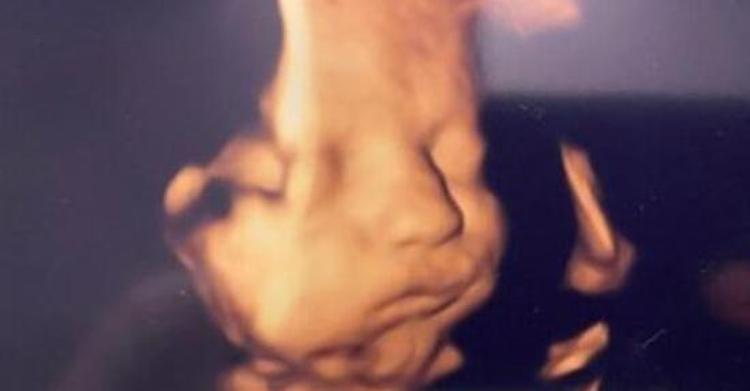

plasenta nedir hamilelik